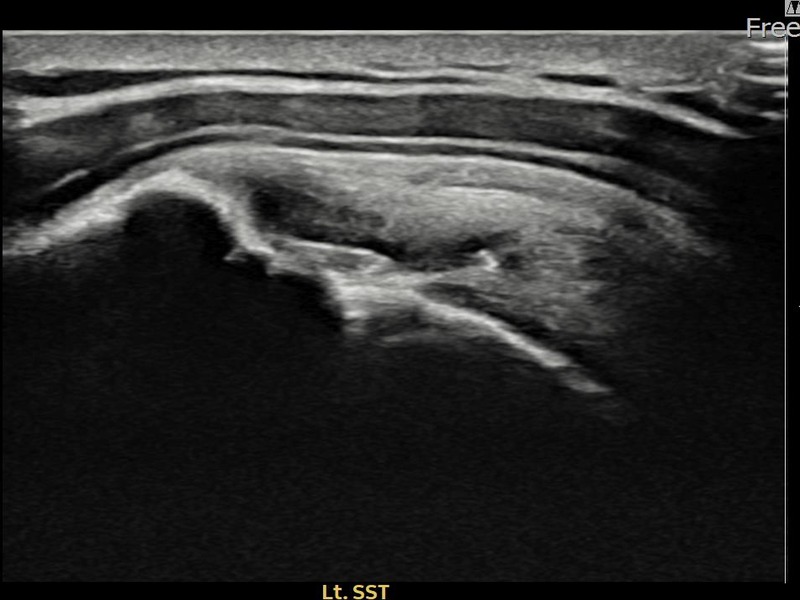

김ㅇㅇ님 · 좌측 극상근건 부착부 광범위 부분파열

좌측 어깨 극상근건 광범위 파열로 수개월간 일상생활이 어렵던 중 내원하셨습니다. 초음파 검사에서 부착부 광범위 부분파열이 확인되었으며, 어깨인대 축소봉합술 시행 후 힘줄 구조가 회복되었습니다.